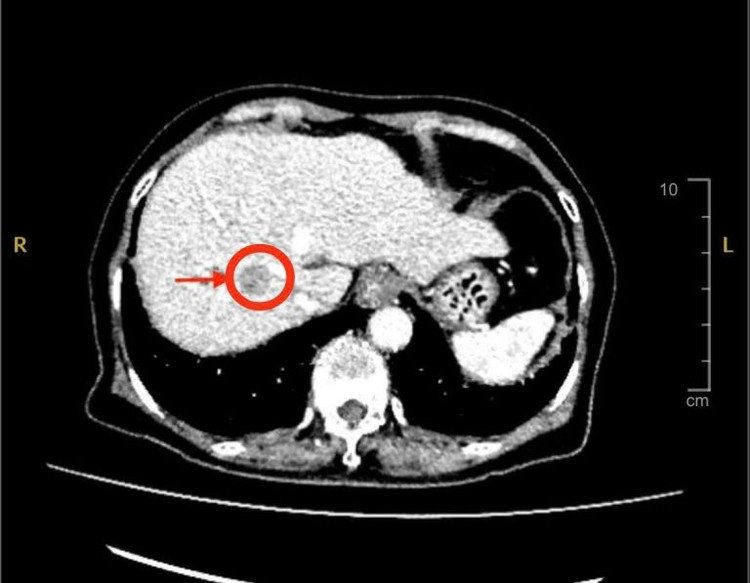

Với tiền sử bệnh xơ gan đang theo dõi và điều trị, xơ gan lại là yếu tố nguy cơ cao của ung thư gan, các bác sĩ nghi ngờ đây có thể là dấu hiệu đầu tiên của bệnh. Vì thế, bác sĩ chỉ định cho bệnh nhân siêu âm bụng và chụp MSCT thì phát hiện có khối u gan bên phải với kích thước khoảng 2cm, nghĩ nhiều đến ung thư nguyên phát tế bào gan (HCC) – một dạng ung thư gan phổ biến ở người có bệnh nền xơ gan, viêm gan B hoặc viêm gan C.

Hình ảnh CT khối u gan - Ảnh BVCC